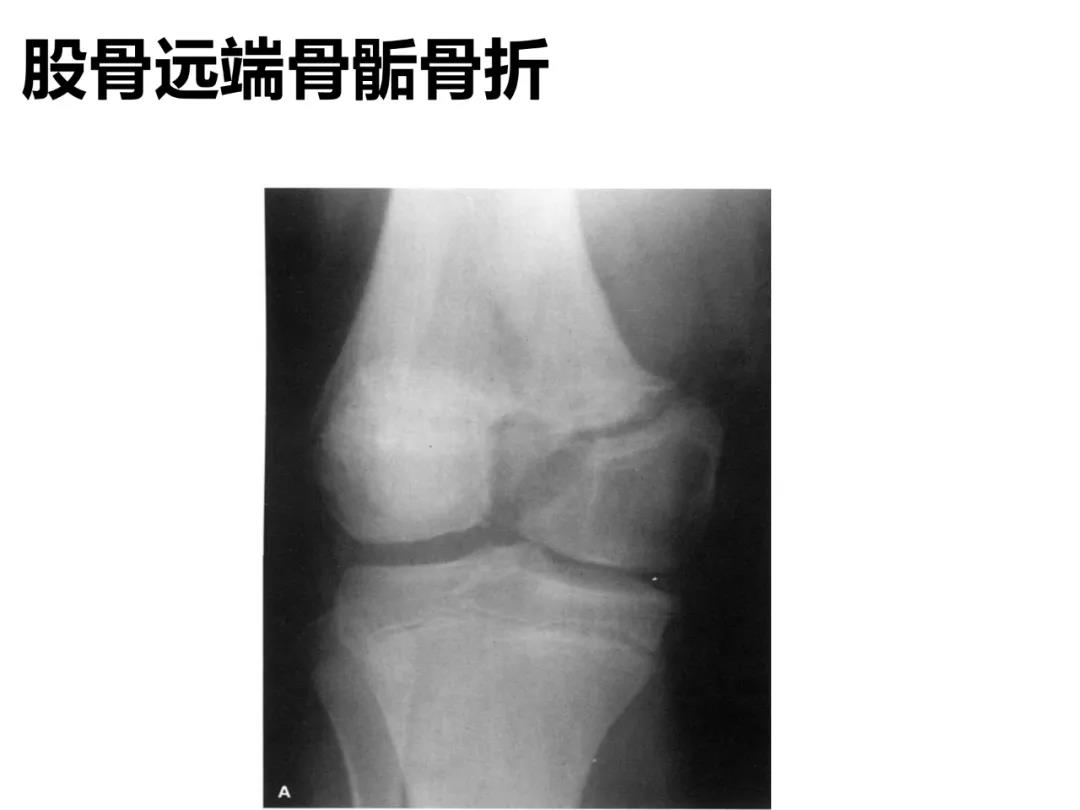

小儿骨科X线片汇总,临床读片宝典!